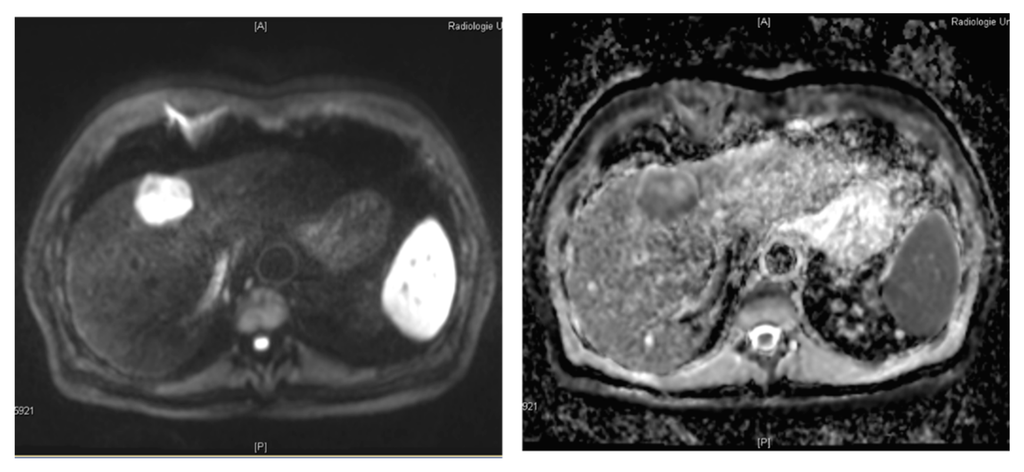

3.2. Diffusion-Weighted MR Imaging

- Koh, D.M.; Collins, D.J. Diffusion-weighted MRI in the body: Applications and challenges in oncology. Am. J. Roentgenol. 2007, 188, 1622–1635. [Google Scholar] [CrossRef] [PubMed]

- Lim, K.S. Diffusion-weighted MRI of hepatocellular carcinoma in cirrhosis. Clin. Radiol. 2014, 69, 1–10. [Google Scholar] [CrossRef] [PubMed]

- Di Pietropaolo, M.; Briani, C.; Federici, G.F.; Marignani, M.; Begini, P.; Delle Fave, G.; Iannicelli, E. Comparison of diffusion-weighted imaging and gadoxetic acid-enhanced MR images in the evaluation of hepatocellular carcinoma and hypovascular hepatocellular nodules. Clin. Imaging 2015, 39, 468–475. [Google Scholar] [CrossRef] [PubMed]

- Hwang, J.; Kim, Y.K.; Jeong, W.K.; Choi, D.; Rhim, H.; Lee, W.J. Nonhypervascular hypointense nodules at gadoxetic acid-enhanced MR imaging in chronic liver disease: Diffusion-weighted imaging for characterization. Radiology 2015, 276, 137–146. [Google Scholar] [CrossRef] [PubMed]

- Kim, H.S.; Kim, S.H.; Kang, T.W.; Song, K.D.; Choi, D.; Park, C.K. Value of gadoxetic acid-enhanced and diffusion-weighted MR imaging in evaluation of hepatocellular carcinomas with atypical enhancement pattern on contrast-enhanced multiphasic MDCT in patients with chronic liver disease. Eur. J. Radiol. 2015, 84, 555–562. [Google Scholar] [CrossRef] [PubMed]

- Kim, Y.K.; Kim, Y.K.; Park, H.J.; Park, M.J.; Lee, W.J.; Choi, D. Noncontrast MRI with diffusion-weighted imaging as the sole imaging modality for detecting liver malignancy in patients with high risk for hepatocellular carcinoma. Magn. Reson. Imaging 2014, 32, 610–618. [Google Scholar] [CrossRef] [PubMed]